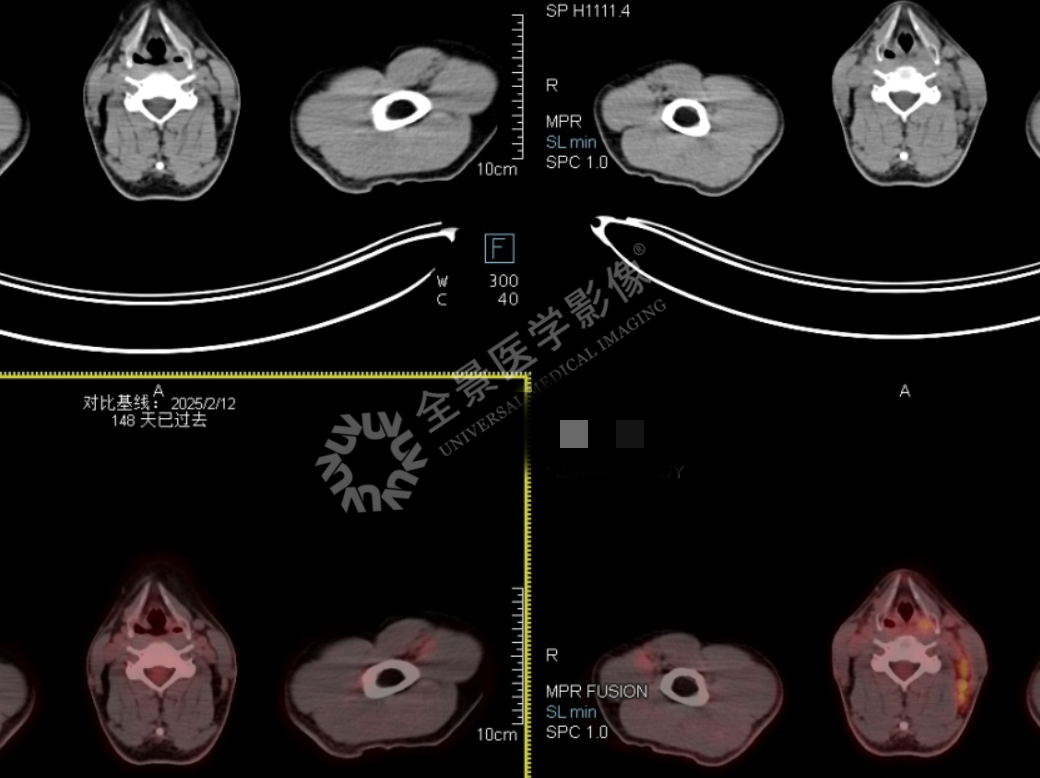

影像示例

影像解读: 确诊滤泡性转化大 B 细胞淋巴瘤,化疗 3 个疗程复查 PET/CT,与 2025‐2‐12 片对比:1. 左侧颈部、锁骨上区(II‐V 区)、右侧颈部(III 区)多发肿大淋巴结,较前明显缩小,部分消失,代谢较前减低 2. 声门上区左侧粘膜稍厚,较前消失;肠系膜及腹膜后多发小淋巴结,较前缩小、消失,现代谢不高以上考虑淋巴瘤治疗后完全响应(多维尔评分 3 分)